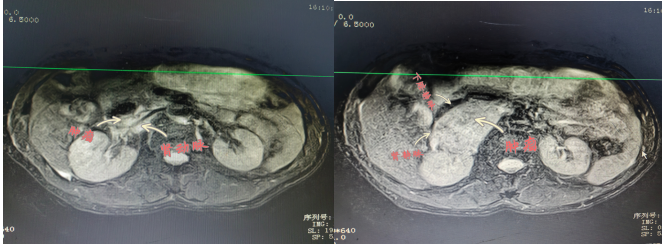

患者陽某,67歲,8月2日因“反復(fù)胸悶氣促2年余,再發(fā)伴頭暈黑蒙3天。”就診于衡陽市中心醫(yī)院心血管內(nèi)科,患者血壓波動大,最高值199/118mmHg,最小值98/57mmHg,射血分?jǐn)?shù)最低42%;完善相關(guān)檢查發(fā)現(xiàn)右腎上腺巨大腫物,大小約57×73×75mm,遂轉(zhuǎn)入衡陽市中心醫(yī)院泌尿外科治療,泌尿外科醫(yī)護(hù)團(tuán)隊(duì)前期做了充分的準(zhǔn)備,并進(jìn)行科內(nèi)討論,麻醉科、心血管內(nèi)科專家會診,充分予以穩(wěn)定血壓、心率和擴(kuò)容等術(shù)前處理。

2022年9月15日,醫(yī)院為患者行腹腔鏡下右側(cè)腎上腺瘤腫瘤切除術(shù),術(shù)中,患者右側(cè)腎上腺腫瘤于腎門,壓迫下腔靜脈,右腎靜脈移位,包繞右腎動脈。腫瘤體積大,血運(yùn)豐富與周圍組織邊界不清, 與大血管粘連,手術(shù)風(fēng)險(xiǎn)極大,術(shù)中鉗夾,擠壓腎上腺瘤體導(dǎo)致腎上腺激素釋放,手術(shù)中血壓的急劇變化。充分顯露手術(shù)視野,仔細(xì)、輕柔操作對腫瘤切除十分關(guān)鍵。麻醉科主任譚滇湘全程護(hù)航。由于準(zhǔn)備充分、配合到位,雖術(shù)中情況多變,最終手術(shù)成功。術(shù)后病檢結(jié)果顯示腫瘤完整切除?;颊咝g(shù)后恢復(fù)良好,于2022年9月24康復(fù)出院。